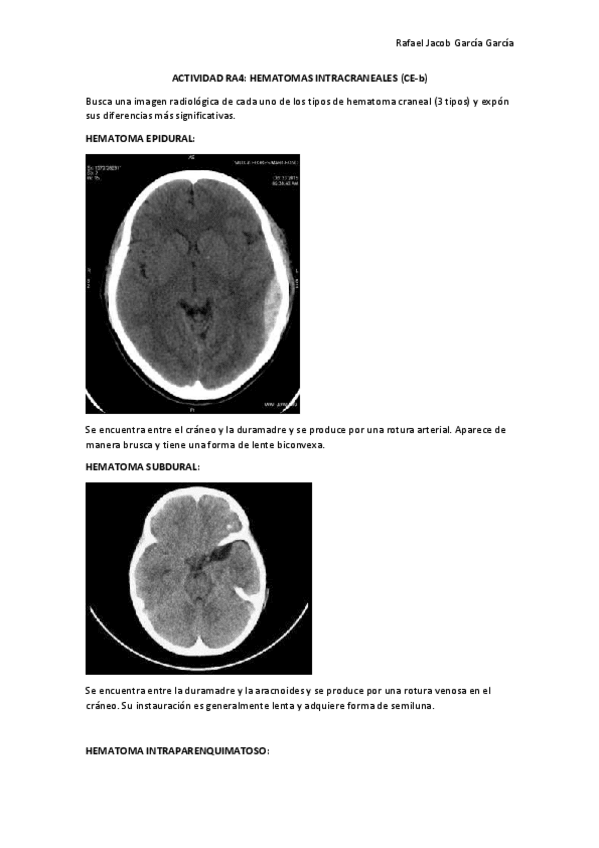

He publicado nuevos ejercicios de Citología general: ACTIVIDAD-RA4-CE-b-hematoma-craneal.pdf

2 páginas